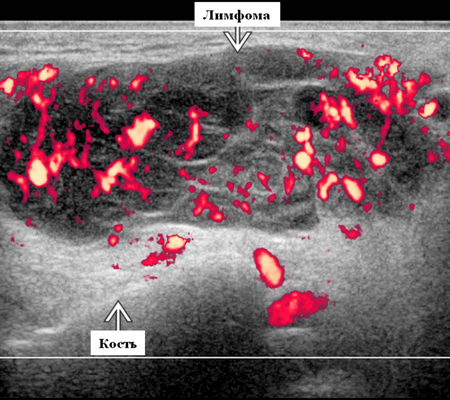

Околоушная неходжкинская лимфома на УЗИ

- Узловая неходжкинская лимфома (НХЛ): одиночные или множественные увеличенные яйцевидные внутрипаротидные лимфатические узлы, которые на УЗИ гомогенно гипоэхогенны по отношению к паренхиме околоушной железы, эхо-картина сетчатая. Заднее акустическое усиление. Выраженная внутриузловая гиперваскуляризация

Лучший диагностический признак на УЗИ при узловой НХЛ: множественные однородные, четко выраженные образования околоушных желез и лимфаденопатия верхних отделов шеи. Паренхиматозная НХЛ: инфильтративная околоушная опухоль, фон СШ, BLEL

Цветной допплер. Узловая НХЛ. Выраженная центральная или внутриузловая гиперваскуляризация. Паренхима при неходжкинской лимфоме более диффузная железистая гиперваскуляризация. Васкуляризация от умеренной до выраженной в плохо очерченных образованиях.